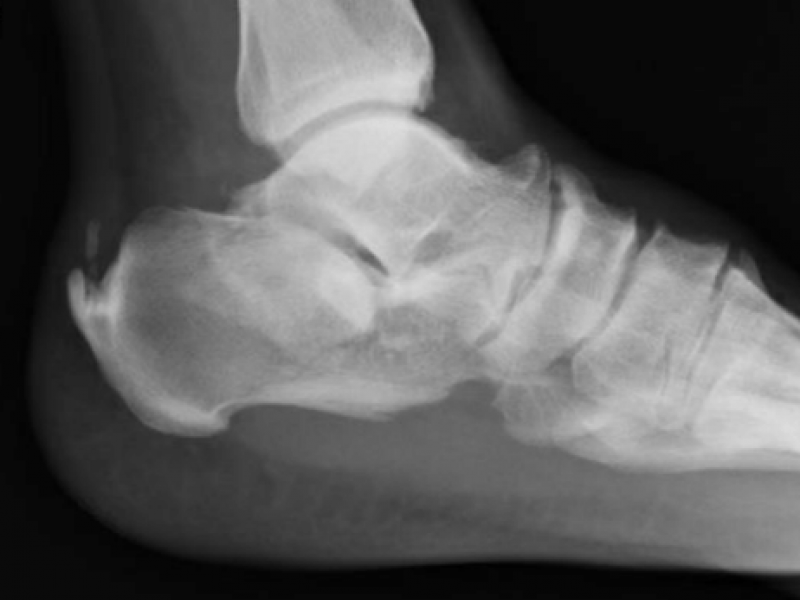

What's the Diagnosis? By Dr. Rebecca Fieles

A 44 yo M presents to the ED w/ L foot and ankle pain. He